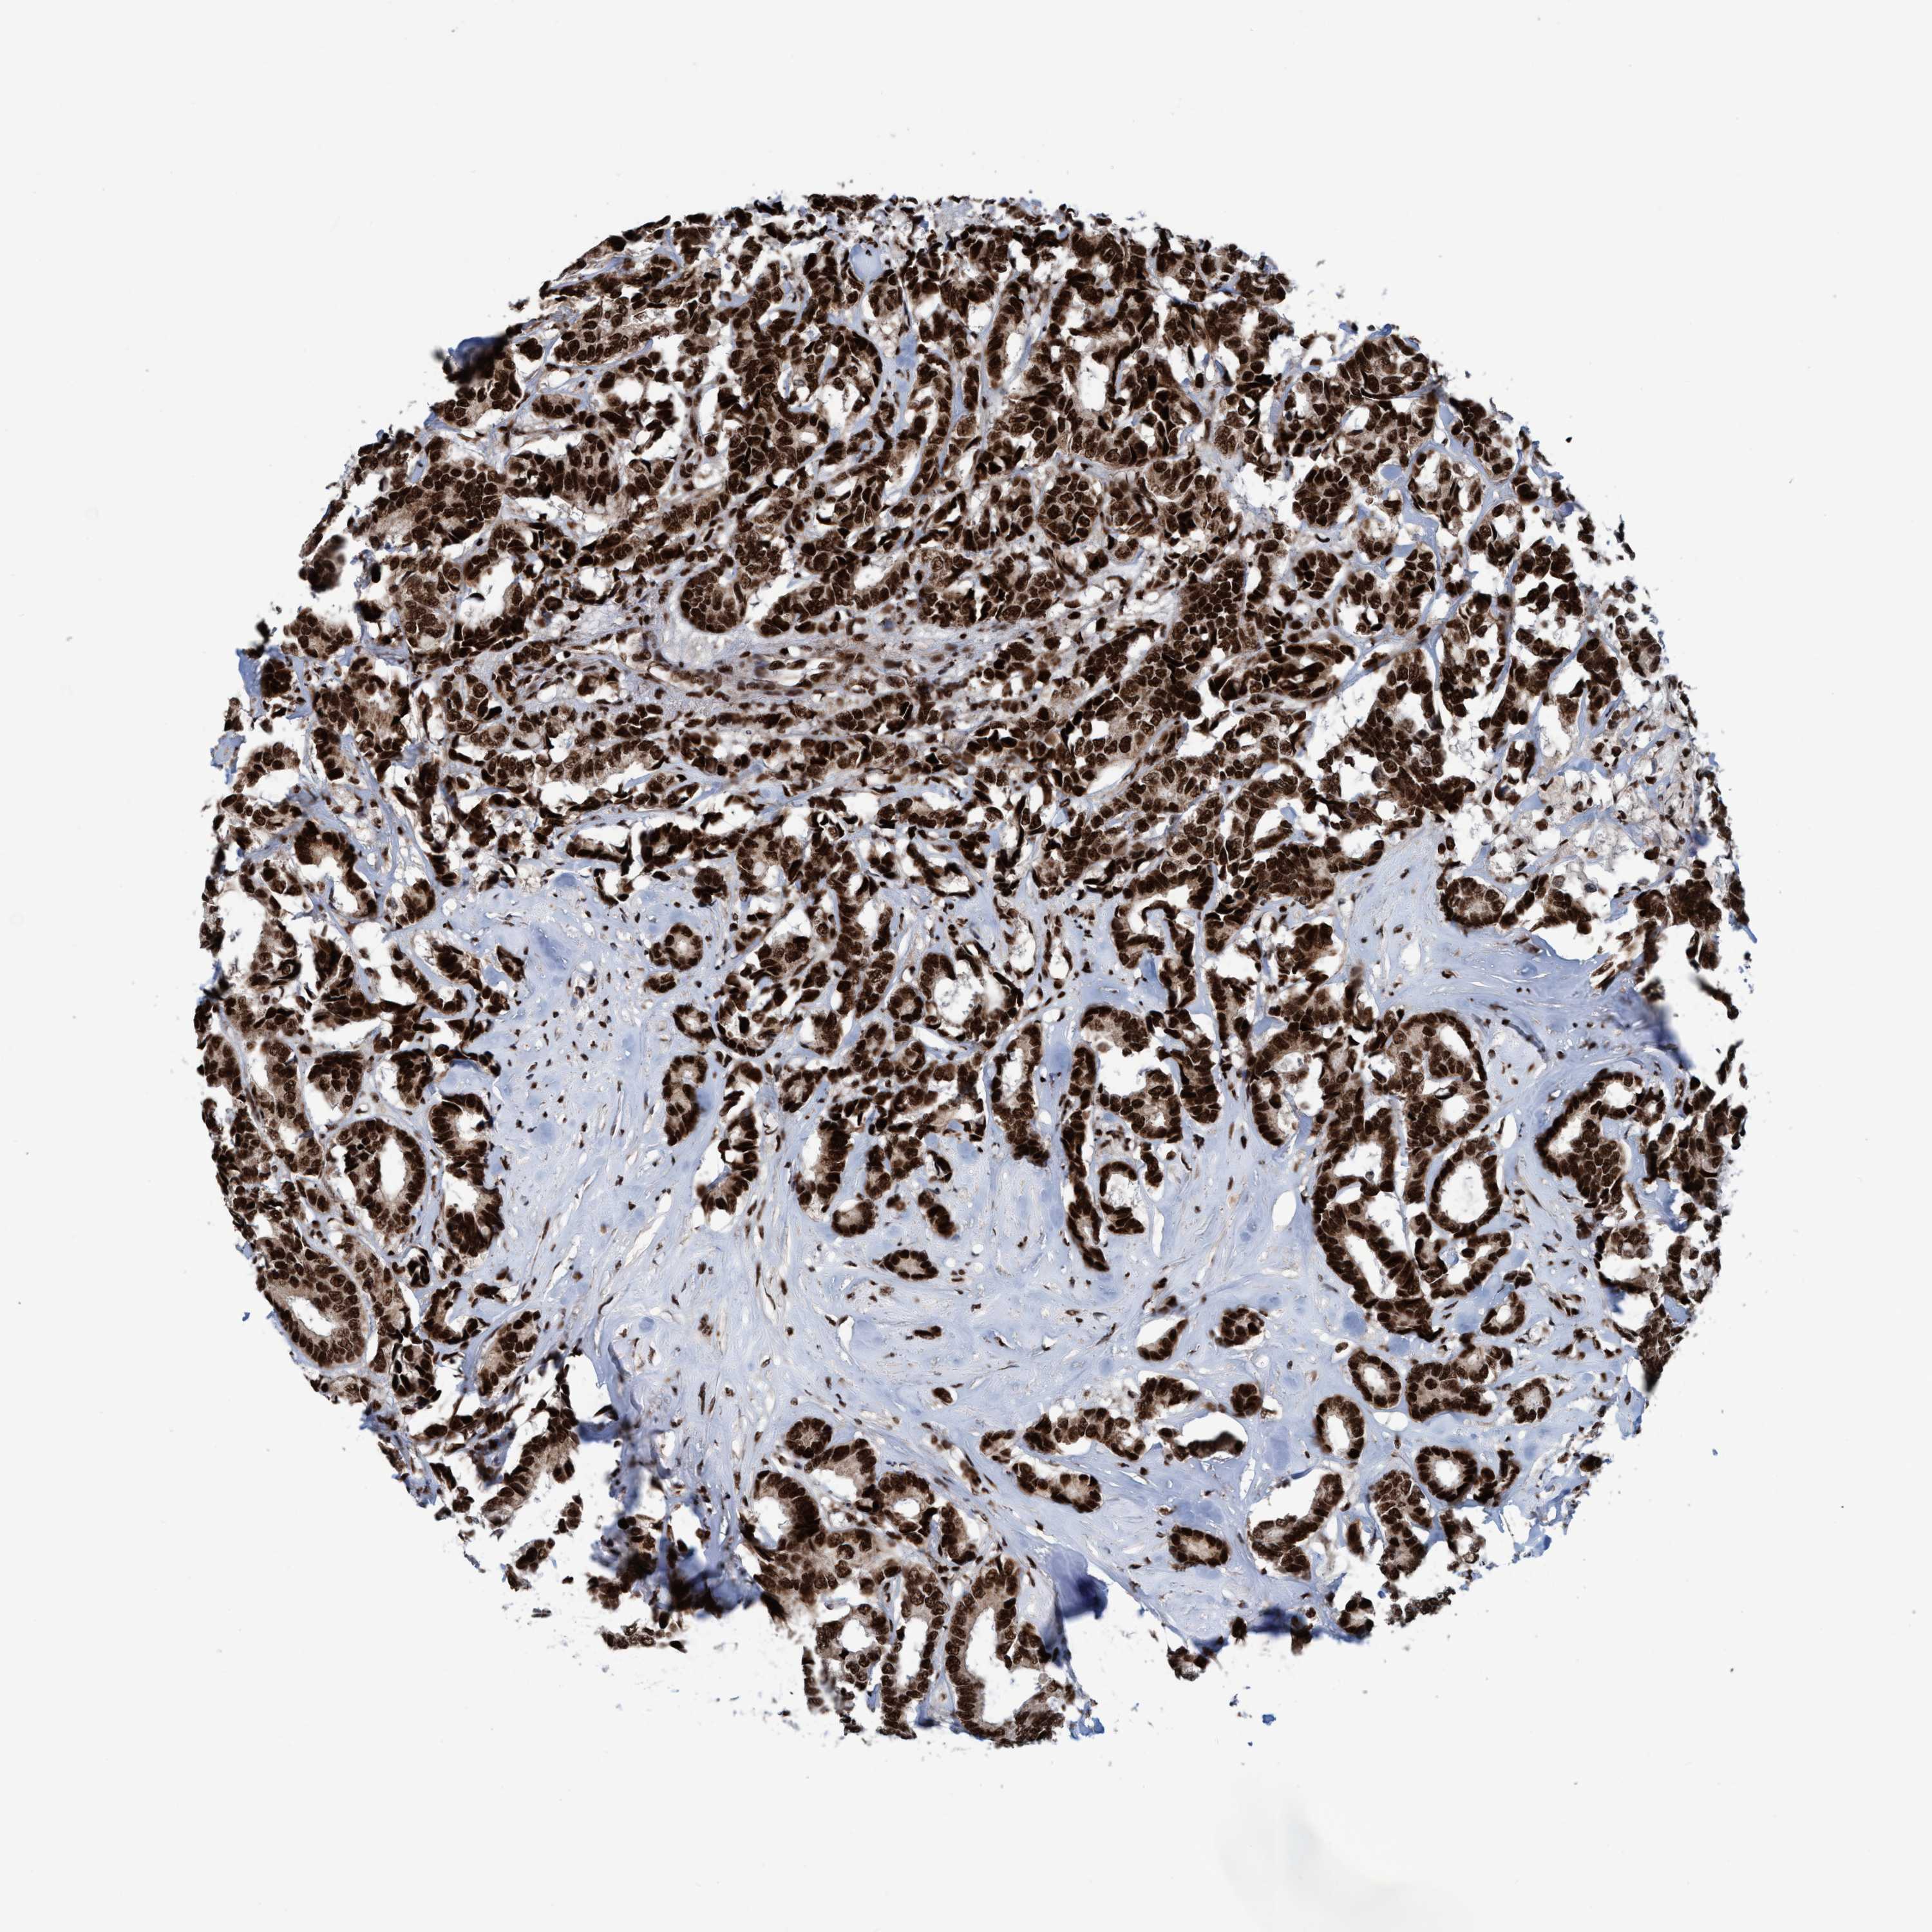

CANCER BREAST CANCER Show tissue menu

BRCA TCGA BRCA VALIDATION PROTEIN EXPRESSION